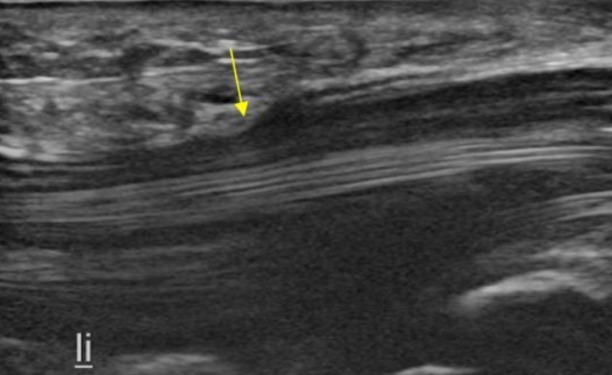

En la siguiente imagen, vemos el caso de una bandera roja. En este corte longitudinal, el nervio mediano aparece comprimido por una masa tumoral en la interfase superficial.

La flecha amarilla indica el punto donde la compresión es más evidente. Al comparar esta zona con la sección a la derecha de la imagen, se aprecia una reducción drástica en el calibre normal del nervio.